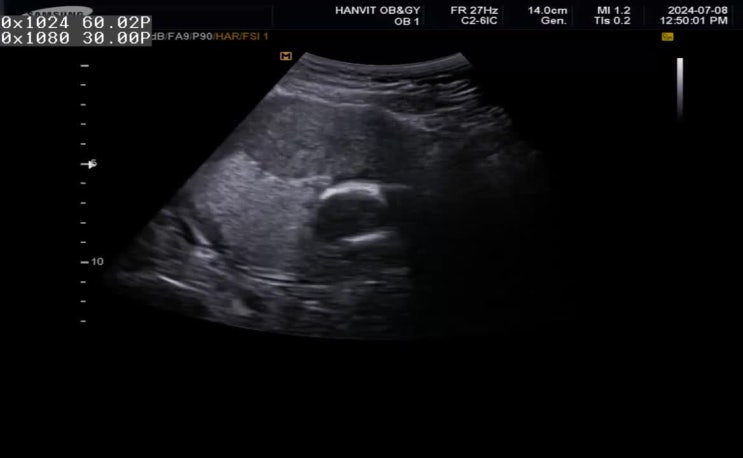

[16주차]드디어, 임신중기입성(조금씩 활동을 시작해보자)/신경관결손검사 결과.

16주차 임신중기 시작! 신경관 결손검사 결과! 2차 기형아검사인 신경관결손 검사 결과를 니프티검사때와 ...